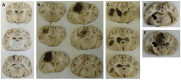

Traumatic brain injury (TBI) remains one of the leading causes of death. Because of the individual nature of the trauma (brain, circumstances and forces), humans experience individual TBIs. This makes it difficult to generalise therapies. Clinical management issues such as whether intracranial pressure (ICP), cerebral perfusion pressure (CPP) or decompressive craniectomy improve patient outcome remain partly unanswered. Experimental drug approaches for the treatment of secondary brain injury (SBI) have not found clinical application. The complex, cellular and molecular pathways of SBI remain incompletely understood, and there are insufficient experimental (animal) models that reflect the pathophysiology of human TBI to develop translational therapeutic approaches. Therefore, we investigated different injury patterns after acute subdural hematoma (ASDH) as TBI in a post-hoc approach to assess the impact on SBI in a long-term, human-sized porcine TBI animal model. Post-mortem brain tissue analysis, after ASDH, bilateral ICP, CPP, cerebral oxygenation and temperature monitoring, and biomarker analysis were performed. Extracerebral, intraparenchymal-extraventricular and intraventricular blood, combined with brainstem and basal ganglia injury, influenced the experiment and its outcome. Basal ganglia injury affects the duration of the experiment. Recognition of these different injury patterns is important for translational interpretation of results in this animal model of SBI after TBI.